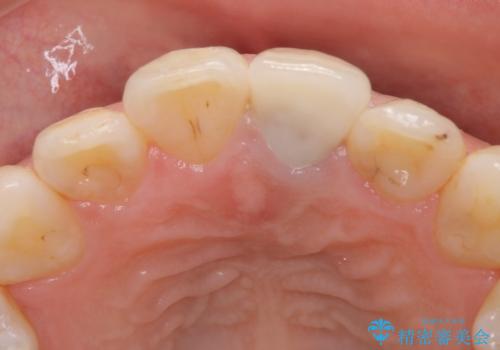

- 矯正前に仮歯にしていた前歯を矯正治療終了後にセラミックによる治療を希望された患者様です。

プラスチックのものから綺麗なセラミックになり喜んでいただきました。